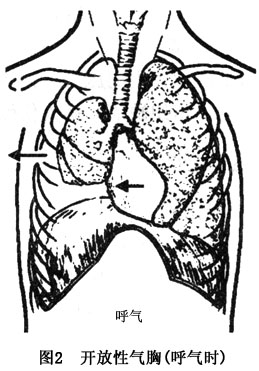

傷側肺可完全萎陷,縱隔推移至對側,壓迫健側肺,通氣不足,塌陷肺泡區域的血液不能氧合,肺動、靜脈分流增加,引起全身缺氧及二氧化碳蓄積。吸氣時傷側肺內部分殘氣吸入健側肺內,呼氣時健側肺部分殘氣進入患側肺內,稱爲縱隔撲動。加重缺氧及二氧化碳瀦留(圖1,2)。